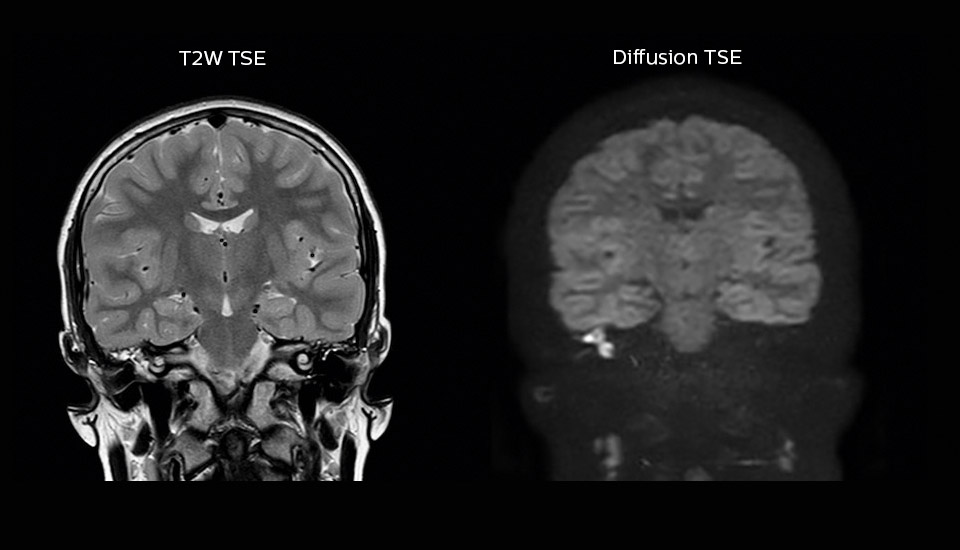

“Imaging cholesteatoma, benign tumors of the middle ear, has been a huge challenge,” says Dr. Heggelman. “We used to do CT, but then we were unsure if we were looking at an inflammation or a cholesteatoma. Also determining if residual cholesteatoma exist after surgery or visualizing recurrence used to be very difficult. Adding Diffusion TSE in our MRI protocol now effectively addresses this.” “Diffusion TSE is far less sensitive to susceptibility differences than previously used EPI sequences. We appreciate the high resolution and the robustness of the sequence. The quality is so good that our confidence has increased. Also our ENT (ear, nose, throat) physicians are excited about the high resolution, the excellent lesion delineation and the sensitivity and specificity.”

“We also love MultiVane XD for motion reduction in imaging. We find this a huge step forward. We use it in the head, and of course in the upper abdomen, and the images are outstanding most of the time. And it can be combined with dS SENSE parallel imaging for speed.” “We have compared image quality of FLAIR with MultiVane XD versus FLAIR without MultiVane XD. In 15 of the 40 patients studied, we saw motion artifacts on plain FLAIR brain images. The FLAIR images with MultiVane XD were motion-free in 39 of 40 patients and showed slight motion artifacts in only one patient.”